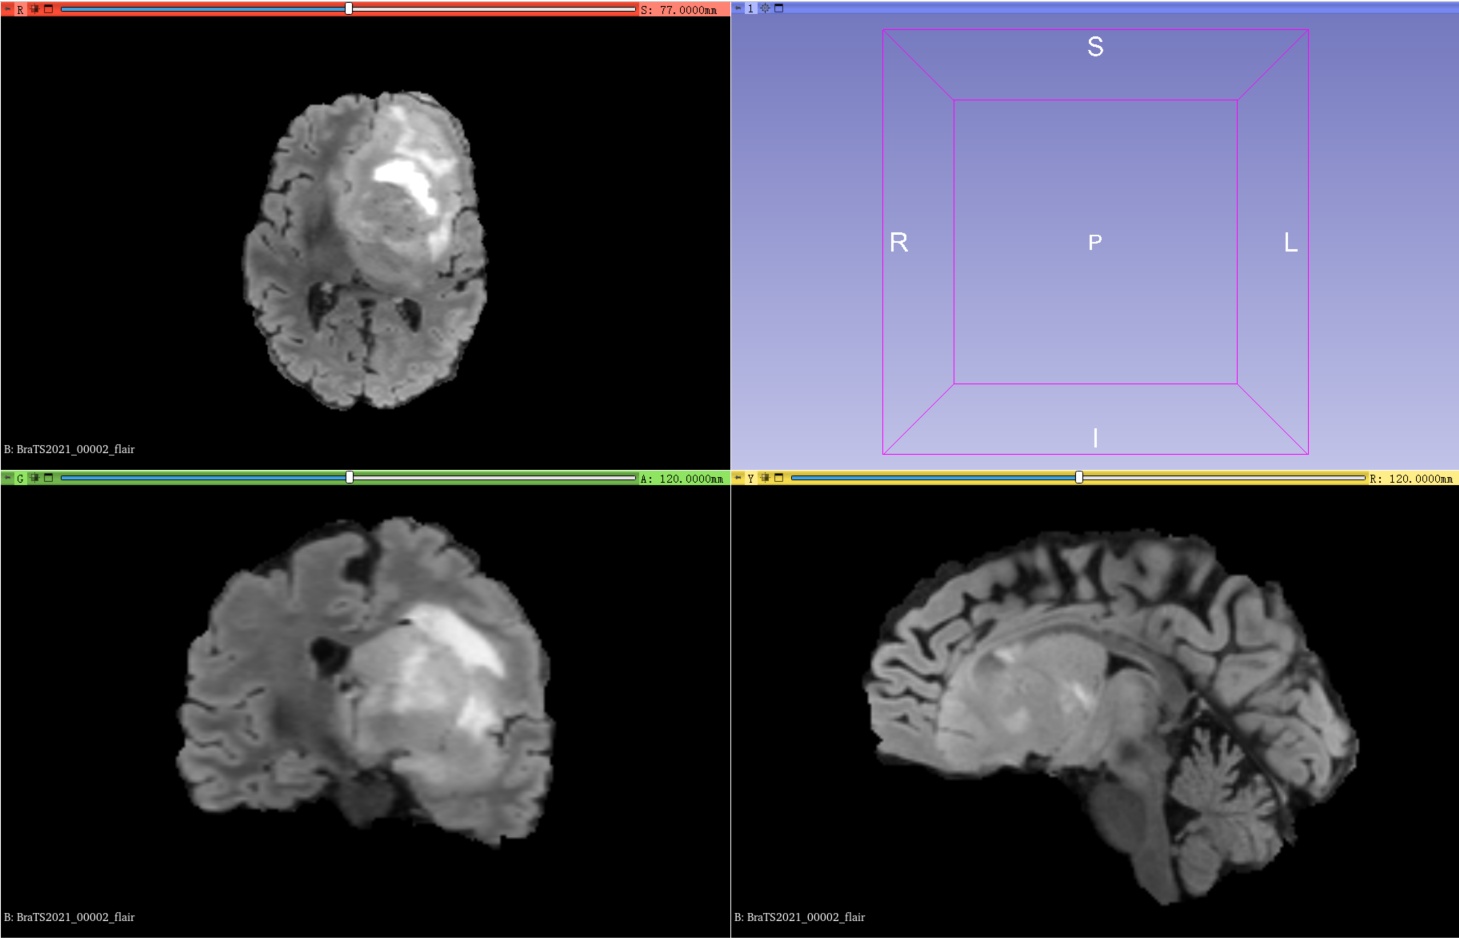

训练集其中一例MRI扫描(包含4个模态的3D图像以及1个共享标签)

1、在训练集中包含1251例核磁共振成像扫描,每例扫描包含4种模态的3D图像以及1个共享标签,其中4种模态分别是t1、t1ce、t2、flair:

FLAIR (Fluid Attenuated Inversion Recovery)成像:这种成像方式通过将T2序列与T1序列结合起来,使用反转恢复脉冲序列,增强了病变和脑脊液的对比度。FLAIR序列主要用于显示肿瘤、炎症和其他异常组织。

BraTS2021_00002_flair.nii.gz |

4、可视化使用3D Slicer查看图像和标签,可以直观的了解自己要用的数据集。左上角代表在Axial(轴向)视角下,可以查看由上到下的脑部二维切片;左下角代表在Coronal(冠状)视角下,可以查看由前到后的脑部二维切片;右下角代表在Sagittal(矢状)视角下,可以查看由左到右的脑部二维切片。

5、用3D Slicer打开BraTS2021_00002_flair.nii.gz,紧接着打开BraTS2021_00002_seg.nii.gz,可以看到在FLAIR 成像时所标注的标签,其他模态亦是如此。